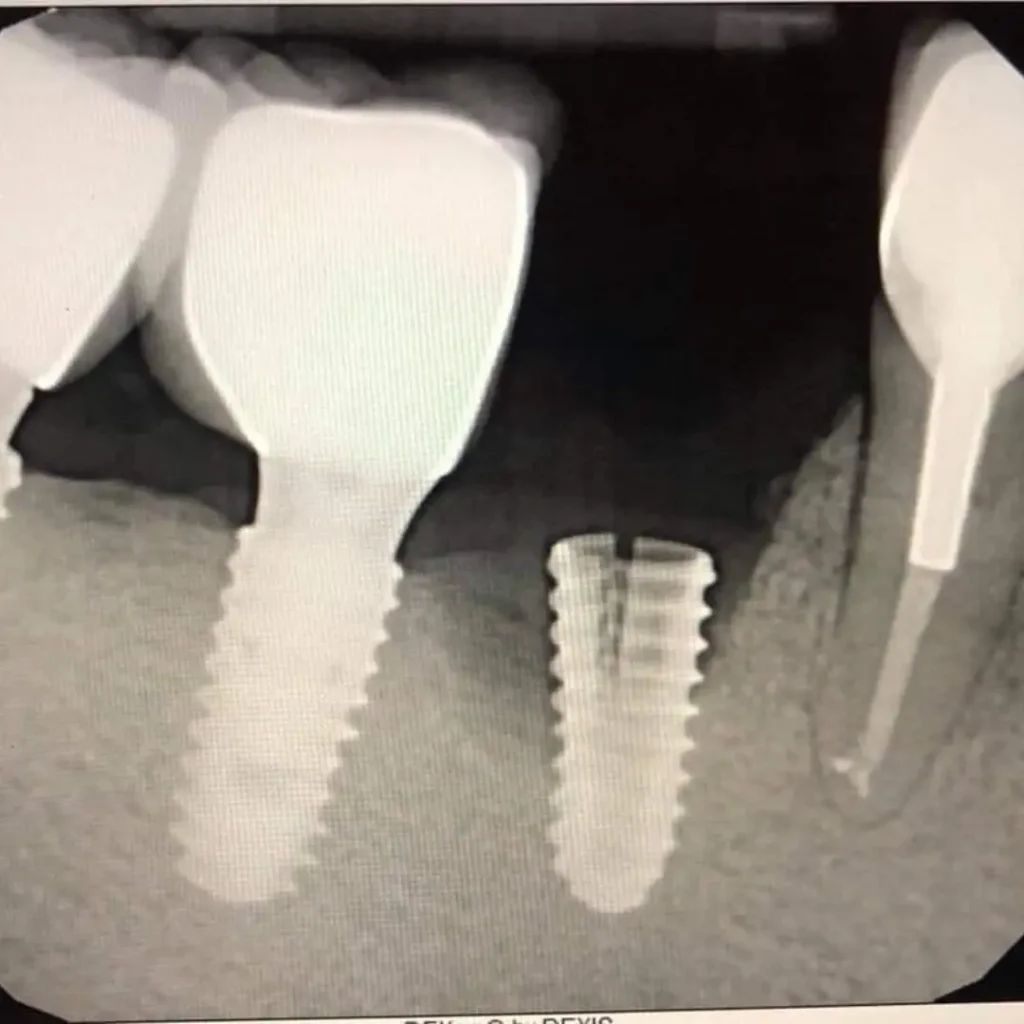

What if I don’t have enough bone for an implant?

In cases where there’s bone loss, a bone graft may be required to rebuild the area before the dental implant procedure. Our specialists will evaluate your condition and develop a personalized treatment plan.

How does an implant differ from a dental bridge?

A dental implant replaces both the natural tooth and its tooth root, making it more stable and long-lasting. A dental bridge relies on adjacent teeth for support. We’ll help you decide which option suits your case best.